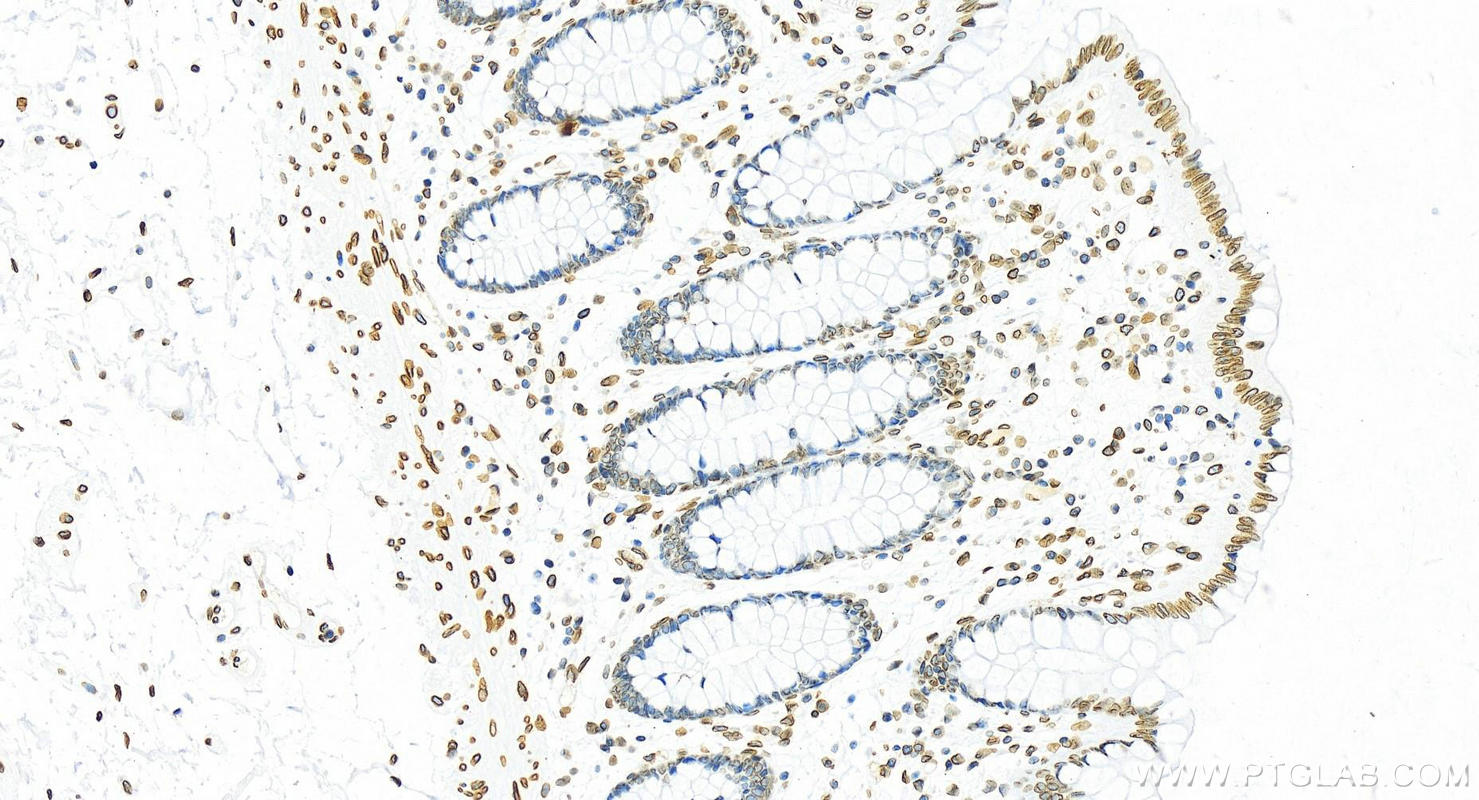

82801-4-PBS targets Lamin B2 in WB, IHC, IF/ICC, FC (Intra), Indirect ELISA applications and shows reactivity with human samples.

| 经测试应用 | WB, IHC, IF/ICC, FC (Intra), Indirect ELISA Application Description |

| 经测试反应性 | human |